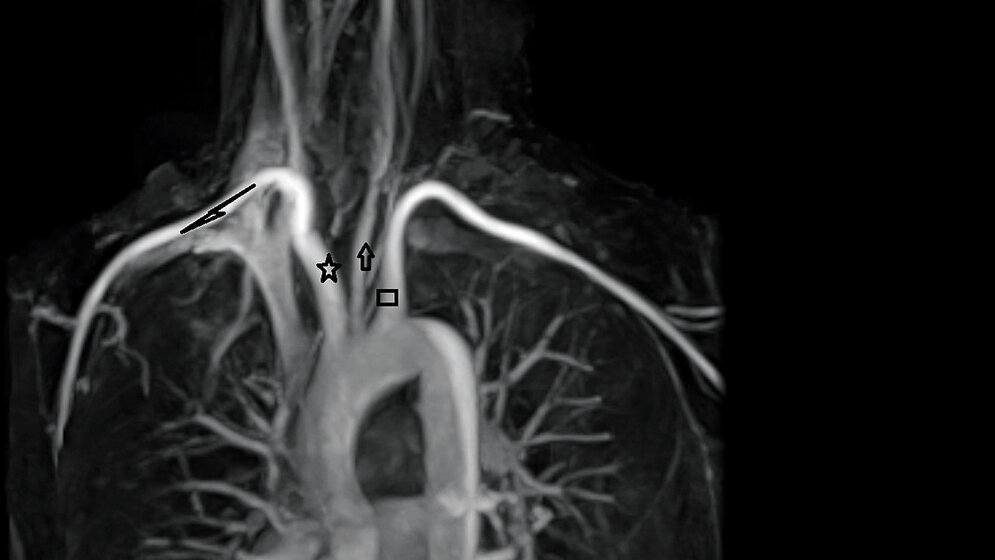

Kongenitale Varianten und Anomalien des Aortenbogens sind bedeutend und können mit anderen Gefäß- und angeborenen Herzerkrankungen sowie chromosomalen Aberrationen vergesellschaftet sein mit entscheidendem Einfluss auf die Prognose und das Management der Erkrankung. Die Arteria lusoria verläuft hauptsächlich retroösophageal und hat eine leichte Prädominanz beim weiblichen Geschlecht. Die Inzidenz ist höher bei Trisomie 21.

Congenital variants and anomalies of the aortic arch are important to recognize as they may be associated with vascular rings, congenital heart disease, and chromosomal abnormalities, and can have important implications for prognosis and management. The arteria lusoria follows a retroesophageal course in most cases and has a female predominance. The incidence is higher in trisomy 21.